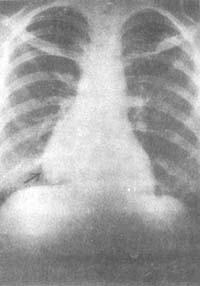

(四)胸部X线检查

常规胸部平片仍是目前比较简单的检查方法,对胸腺瘤的诊断可达62%。胸腺纵隔区体层摄影可发现30%胸片阴性的病例有胸腺瘤。胸部CT诊断符合率达94%,CT扫描可鉴别囊性或实性,有否钙化并能发现较小的胸腺瘤,也可看出有否侵犯胸膜、肺及大血管等恶性胸腺瘤的指征。

图1 后前位胸片示:右心缘旁阴影

男,58岁,重症肌无力合并胸腺瘤患者

图2 右侧位胸部体层像示:

前纵隔阴影(同上例)